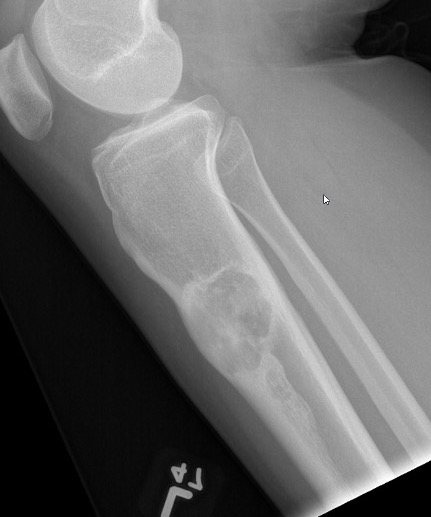

X-ray

Multiple small radiolucent lesions surrounded by sclerosis

Thickened cortex

Doesn't progress on xray

Most common anterior cortex of tibia

Soap-bubble appearance

Eccentrically located

- well circumscribed

- slightly expansile

- cortical thickening

- little or no periosteal reaction